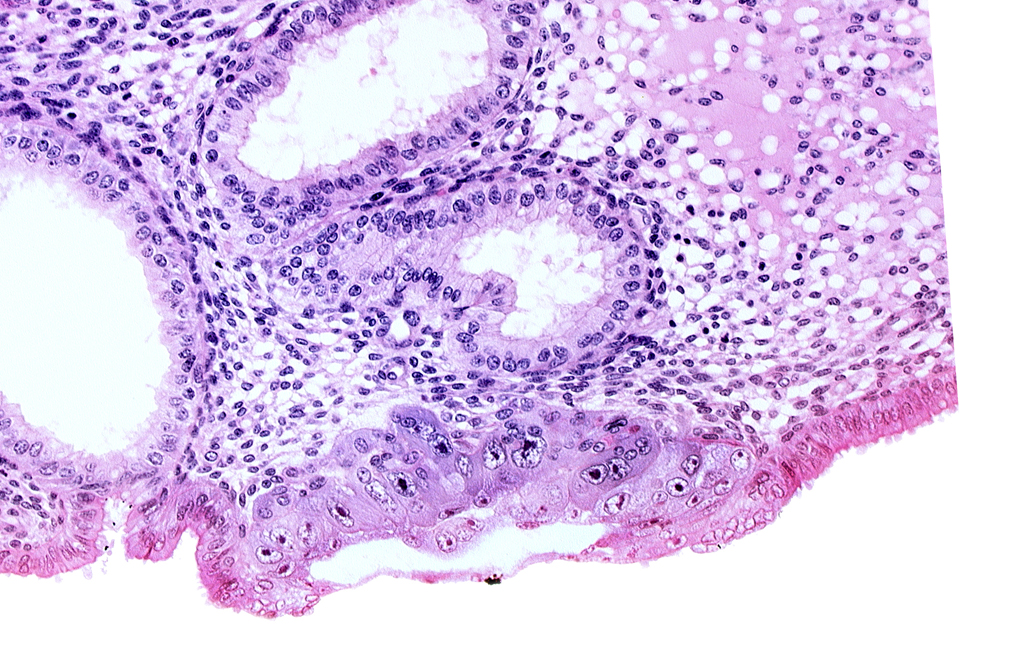

Carnegie Embryo #8020 | Location: 06-02-09

Keywords: amniotic cavity, edematous endometrial stroma (decidua), embryonic disc, endometrial epithelium, extra-embryonic mesoblast, syncytiotrophoblast / decidua interface

Source: The Virtual Human Embryo.